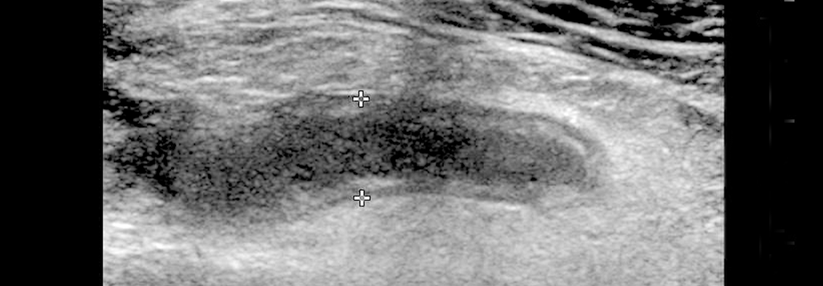

In der Speiseröhre stößt man nur selten und eher in der unteren Hälfte auf Tumoren. Am häufigsten handelt es sich um gutartige Leiomyome, erklären die Ludwigsburger Gastroenterologen. Man müsse sie jedoch zwingend von den äußerlich ähnlichen und potenziell malignen gastrointestinalen Stromatumoren (GIST) abgrenzen. Das ist etwas knifflig, denn das subepitheliale Wachstum der beiden erschwert die Diagnose. Abhilfe schaffen kann der endoskopische Ultraschall. Durch Zuordnung der Läsion zu einer bestimmten Wandschicht und durch das Echomuster lassen sich auch solche Gebilde näher klassifizieren.